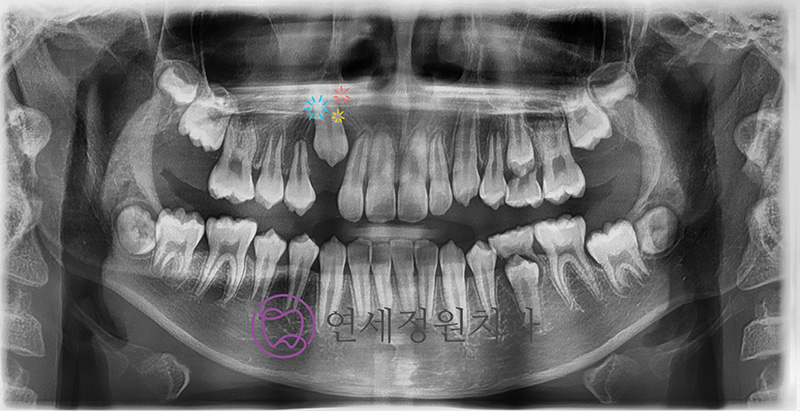

Because his baby teeth were coming out later than usual, I took a panoramic X-ray during a routine check-up. It showed that his upper right canine and first premolar were not aligned properly. The premolar was tilted backward, blocking the canine from erupting.

After about six months, his follow-up X-ray showed a much-improved eruption angle. He continued wearing the appliance for nearly a year, until the tooth finally erupted through the gums.

His most recent panoramic image shows the canine now erupting in a much healthier position.